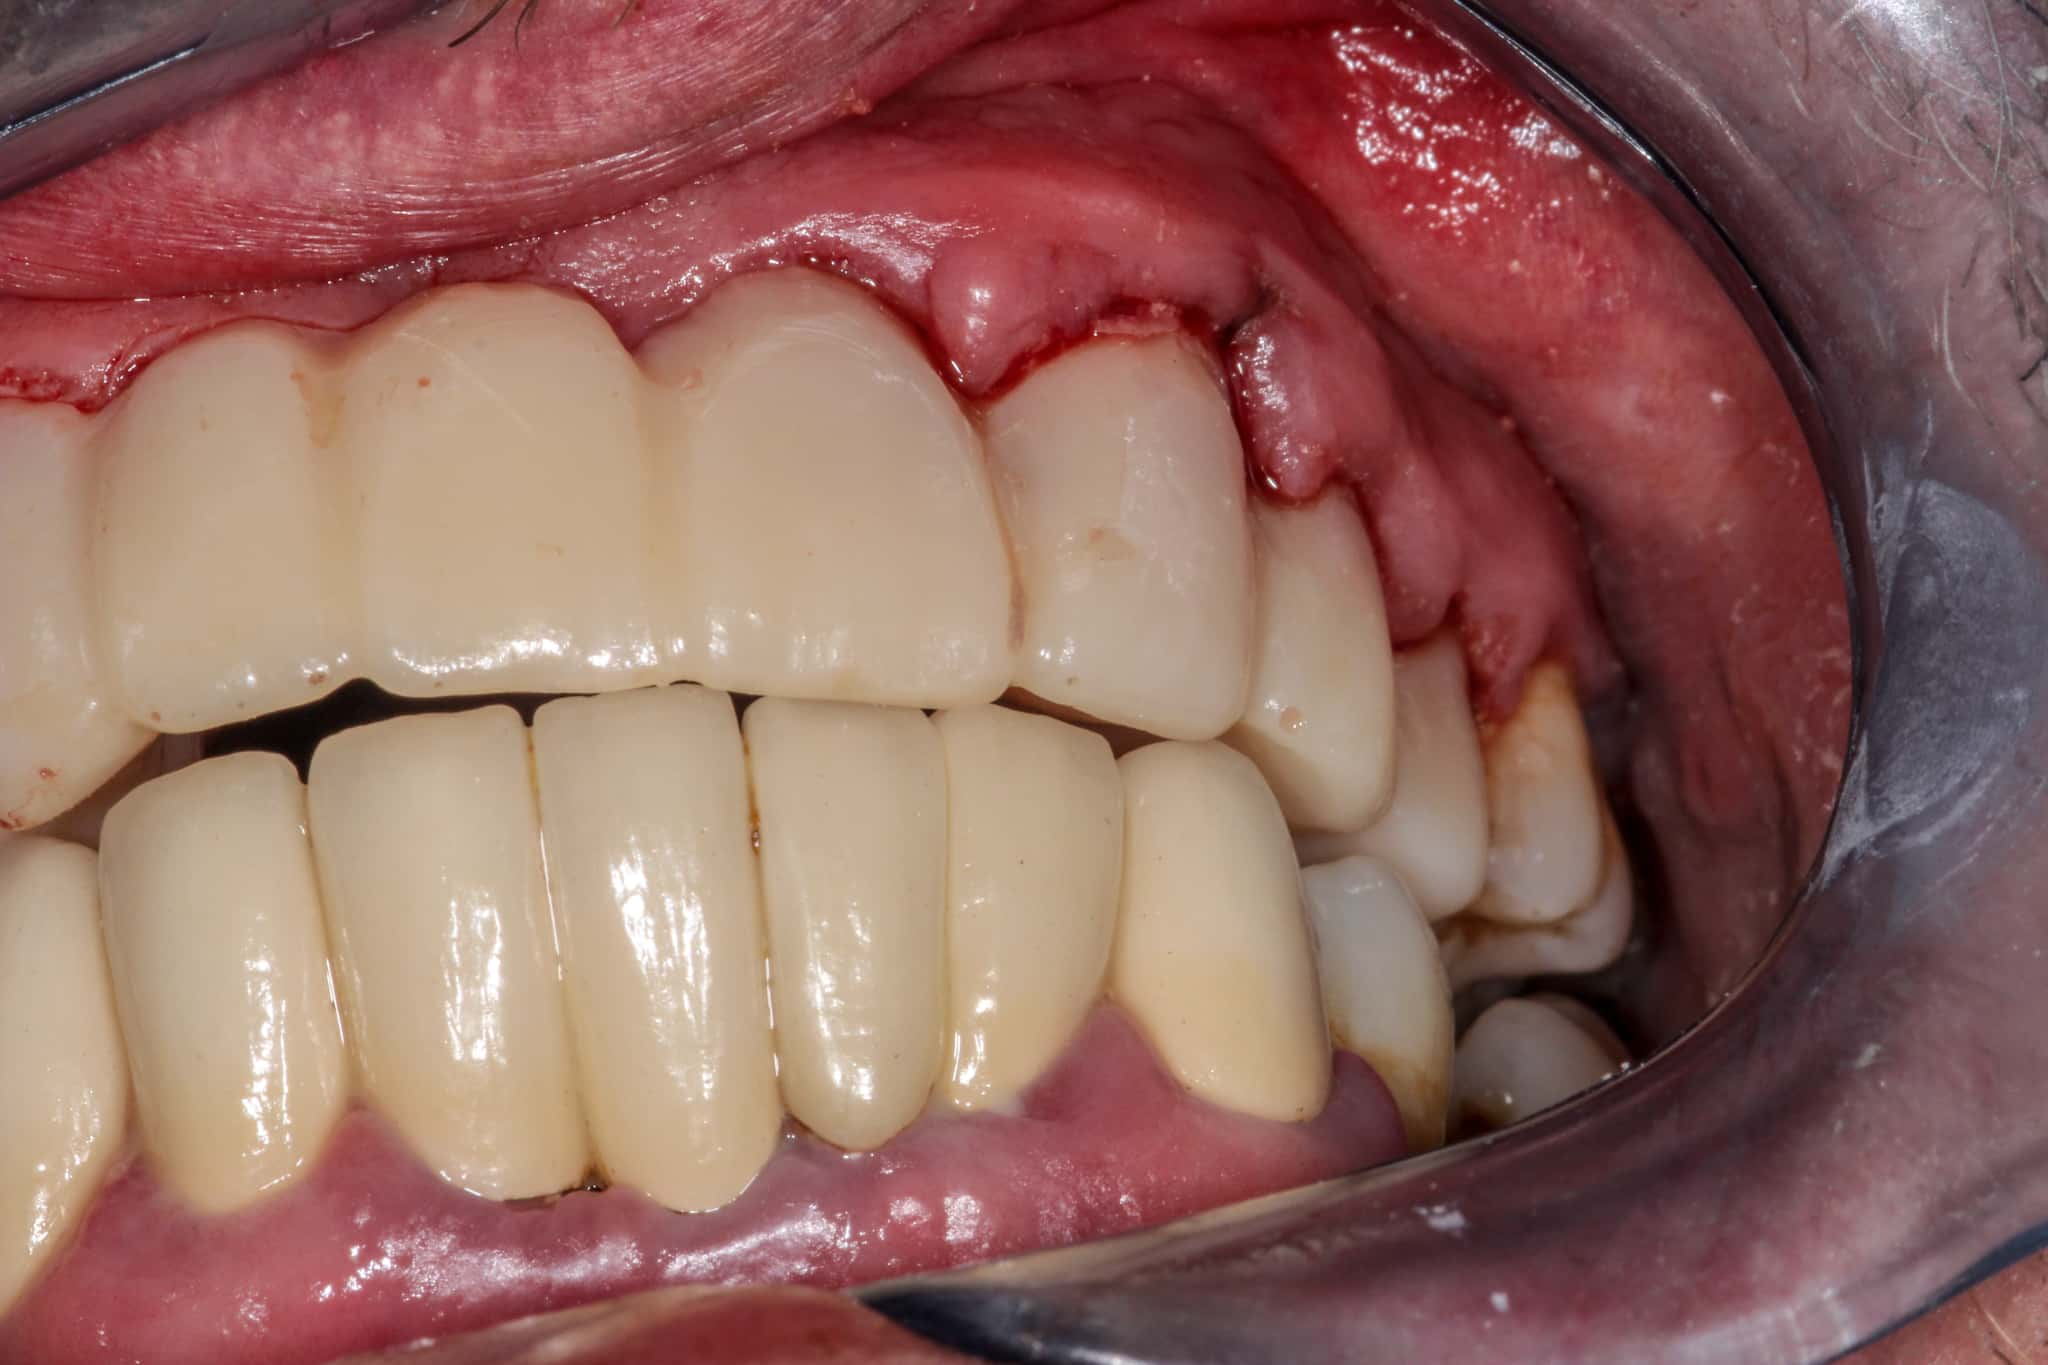

インプラント治療は、失った歯を自然な見た目と機能で補うことができる画期的な治療法です。

しかし、すべての方がすぐにインプラント治療を受けられるわけではありません。特に、顎の骨が少ない状態では、インプラントを固定するための土台が不十分なため、治療に制限が生じることがあります。

顎の骨が少ない場合、インプラント治療が難しいとされることがあります。

インプラントは顎の骨に埋め込む治療であるため、一定の骨の高さや幅が必要です。骨量が不足していると、インプラントがしっかりと固定されず、治療の成功率が下がる可能性があります。

また、骨が薄い箇所に無理に埋入すると、インプラントの破損や脱落のリスクが高まります。

しかし、近年では、骨を再生させる手術や、骨の少ない部分に対応した治療法があり、顎の骨が少ない方でもインプラントを受けられるケースが増えています。

歯科医師が歯科用CTなどを用いて精密に骨の状態を把握し、適切な術式を選択することで、安全に治療を進めることが可能です。